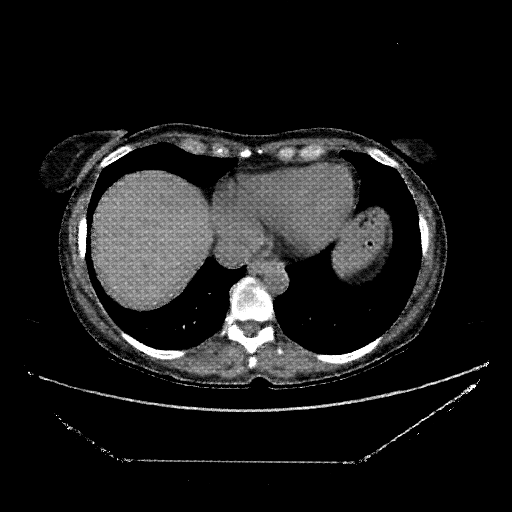

Reconstructed NATIVE CT scan (cycle consistency)

Full window (WL 1023.5, WW 4095 β†’ Low βˆ’1024, High +3071)

Lung window (WL -600, WW 1500 β†’ Low βˆ’1350, High +150)